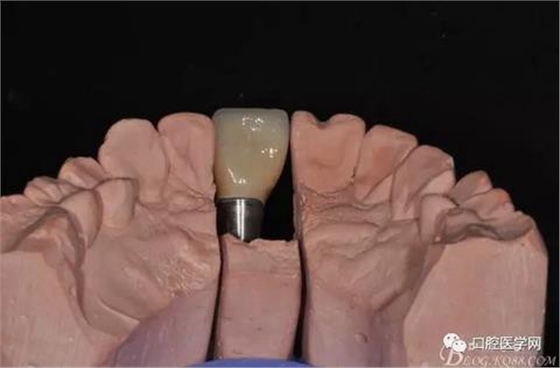

圖16 修復基臺模型頜面照

圖17 烤瓷冠唇側照

圖18 烤瓷冠舌側照